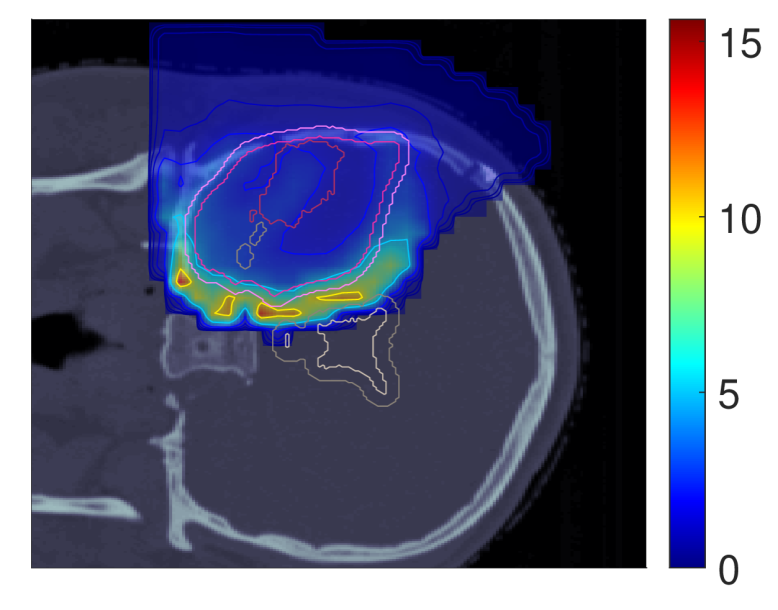

Figure 7 shows the POLO maps resulting from voxel-wise evaluation of the sigmoid-transformed linear predictor η\eta from Equation 1 with the input slice images for dRBE,fxd_{RBE,fx} and ldl_{d}.

NTCP30 %NTCP\approx{$30\text{\,}\mathrm{\char 37\relax}$} NTCP20 %NTCP\approx{$20\text{\,}\mathrm{\char 37\relax}$} NTCP10 %NTCP\approx{$10\text{\,}\mathrm{\char 37\relax}$}

pp (NTCPp)(NTCP_{p})

Refer to caption Refer to caption Refer to caption

pp (LSEp~)(LSE_{\tilde{p}})

pp (H~p)(\tilde{H}_{p})

pp (H~p~)(\tilde{H}_{\tilde{p}})

Figure 7: Optimal slice images of the probability of lesion origin pp for NTCPpNTCP_{p}, LSEp~LSE_{\tilde{p}}, H~p\tilde{H}_{p} and H~p~\tilde{H}_{\tilde{p}} at different NTCP levels. Considering the slice images for dRBE,fxd_{RBE,fx} and ldl_{d} from Figure 3 and Figure 5, the calculated pp values can be deduced from the prediction model. For example, hot spots are primarily found where high dRBE,fxd_{RBE,fx} values meet high ldl_{d} values, and for the voxels inside the 4 mm4\text{\,}\mathrm{mm} ventricular fringe where bb boosts the probability prediction. We take from these results that the POLO model-based optimization of the LGG sample patient’s proton plan achieves its goal, i.e., reducing pp in the region of interest.

For NTCPpNTCP_{p} and H~p\tilde{H}_{p}, we observed a (slight) reduction of dRBE,fxd_{RBE,fx} in the target volume and in the lower region overlapping with the VS, as well as a redistribution of ldl_{d} from the target volume to the margin of the PTV. Correspondingly, we see an overall reduction of pp in the target volume, together with an increasing attenuation of the hot spots around the marginal region of the PTV, and an elimination at the lower end of the VS. At strong down-regulation of the NTCP, the values are approximately one order of magnitude smaller, with peaks in the intersections to the 4 mm4\text{\,}\mathrm{mm} ventricular fringe and in regions where dRBE,fxd_{RBE,fx} and ldl_{d} intensify.

LSEp~LSE_{\tilde{p}} showed a decay of dRBE,fxd_{RBE,fx} inside but not outside the target volume, and almost constant values of ldl_{d}, and we recognize this pattern again in the pp distributions: hot spots are softened by the isolation of high-dose and high-LET regions, and the pp values in the target volume follow the negative trend for dRBE,fxd_{RBE,fx} at lower NTCP levels. Even the “dose gap” that occurs at an NTCP of 20 %20\text{\,}\mathrm{\char 37\relax} in the upper part of the target volume can be read from pp. Last, for H~p~\tilde{H}_{\tilde{p}} we can correlate the results for dRBE,fxd_{RBE,fx} and ldl_{d} again to understand pp. The higher ldl_{d} along the PTV margin is reflected by larger pp values and local hot spots, while the region around the GTV exhibits smaller pp values due to the reduction of dRBE,fxd_{RBE,fx}. At the lowest NTCP level, dRBE,fxd_{RBE,fx} contracts around the GTV, leaving only a slightly upward region at the left margin of the PTV which resembles the high-LET region, and hot spots where dRBE,fxd_{RBE,fx}, ldl_{d} and bb interact reinforcingly.

Globally, we observe an analogous shift in the “mass” of the pp distribution to lower values from the histograms in Figure 8. This indicates that the overarching goal of reducing pp during optimization can be fulfilled.